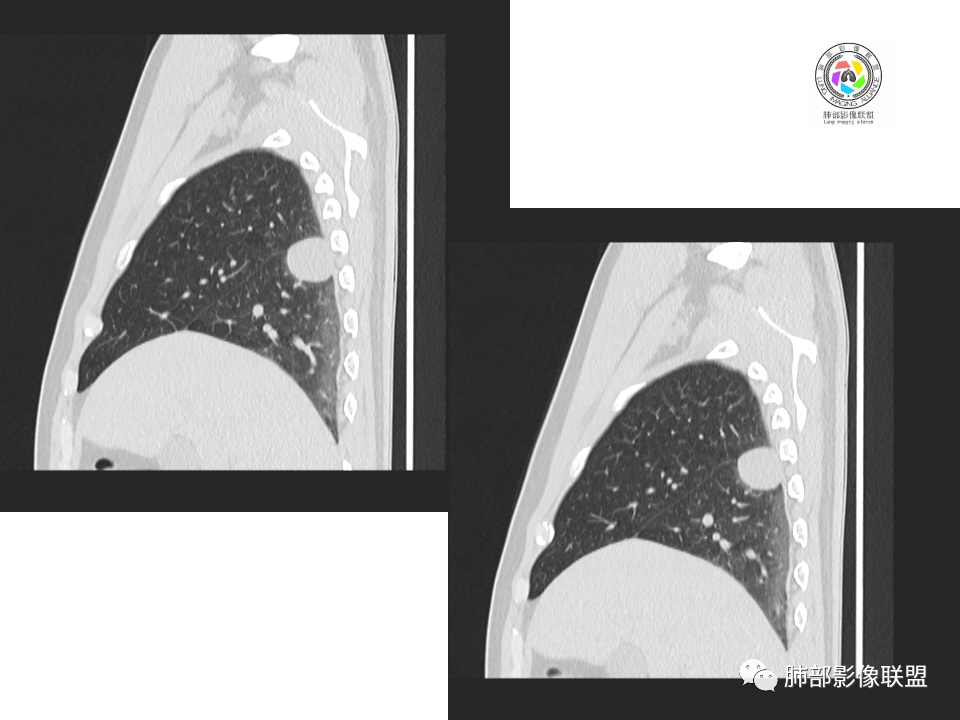

2.右肺下叶背段胸膜下块影,边界清楚光整,上下极见磨玻璃晕,未见明显分叶毛刺和棘状突起,未见胸膜凹陷或胸壁侵入。密度均匀,轻度不均匀强化。未见支气管进入。

4.右肺下叶基底段支气管血管束旁小结节影,边界清楚,强化不明显。注意,这结节在“遥远的”基底段。

中年男性,体检发现占位。右肺下叶背段胸膜下肿块,周围晕征,有小分叶,与支气管、肺内血管关系不清,形似山丘,重建可见肿块呈D字形凸向肺部。似跨斜裂,似有小凸起与肋下缘相连,增强似有轻微均匀强化。右肺下叶外基底段小结节,位于血管周围,部分边缘平直,轻微均匀强化。考虑二元:一、右下叶背段肿块为肺外病变,神经鞘瘤?SFT?鉴别小细胞癌、隐球菌病;二、右下叶外基底段结节考虑为良性结节、炎性肉芽肿?

4.良性占位绕不过去,如发生于该部位的孤立性纤维瘤等……

病灶不均匀强化可以将含液支气管囊肿排除在外。

有老师分析,多发病灶有磨玻璃晕,可以符合隐球菌感染,确实如此。但背段边缘如此锐利的块影还是更容易让人联想到新生物。